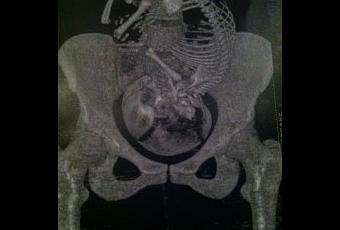

Dans certains cas, vers la fin du huitième mois de la grossesse, on doit s’assurer par une radio ou un scanner que le bassin de la future mère est assez large pour laisser passer l’enfant au moment de l’accouchement. C’est un examen relativement court (environs un quart d’heure), au cours duquel on mesure par radiographie la taille du bassin. C’est une technique totalement indolore.

Les résultats de cette radiographie seront alors analysés et permettront de déterminer si l’accouchement sera par voie basse ou par césarienne.